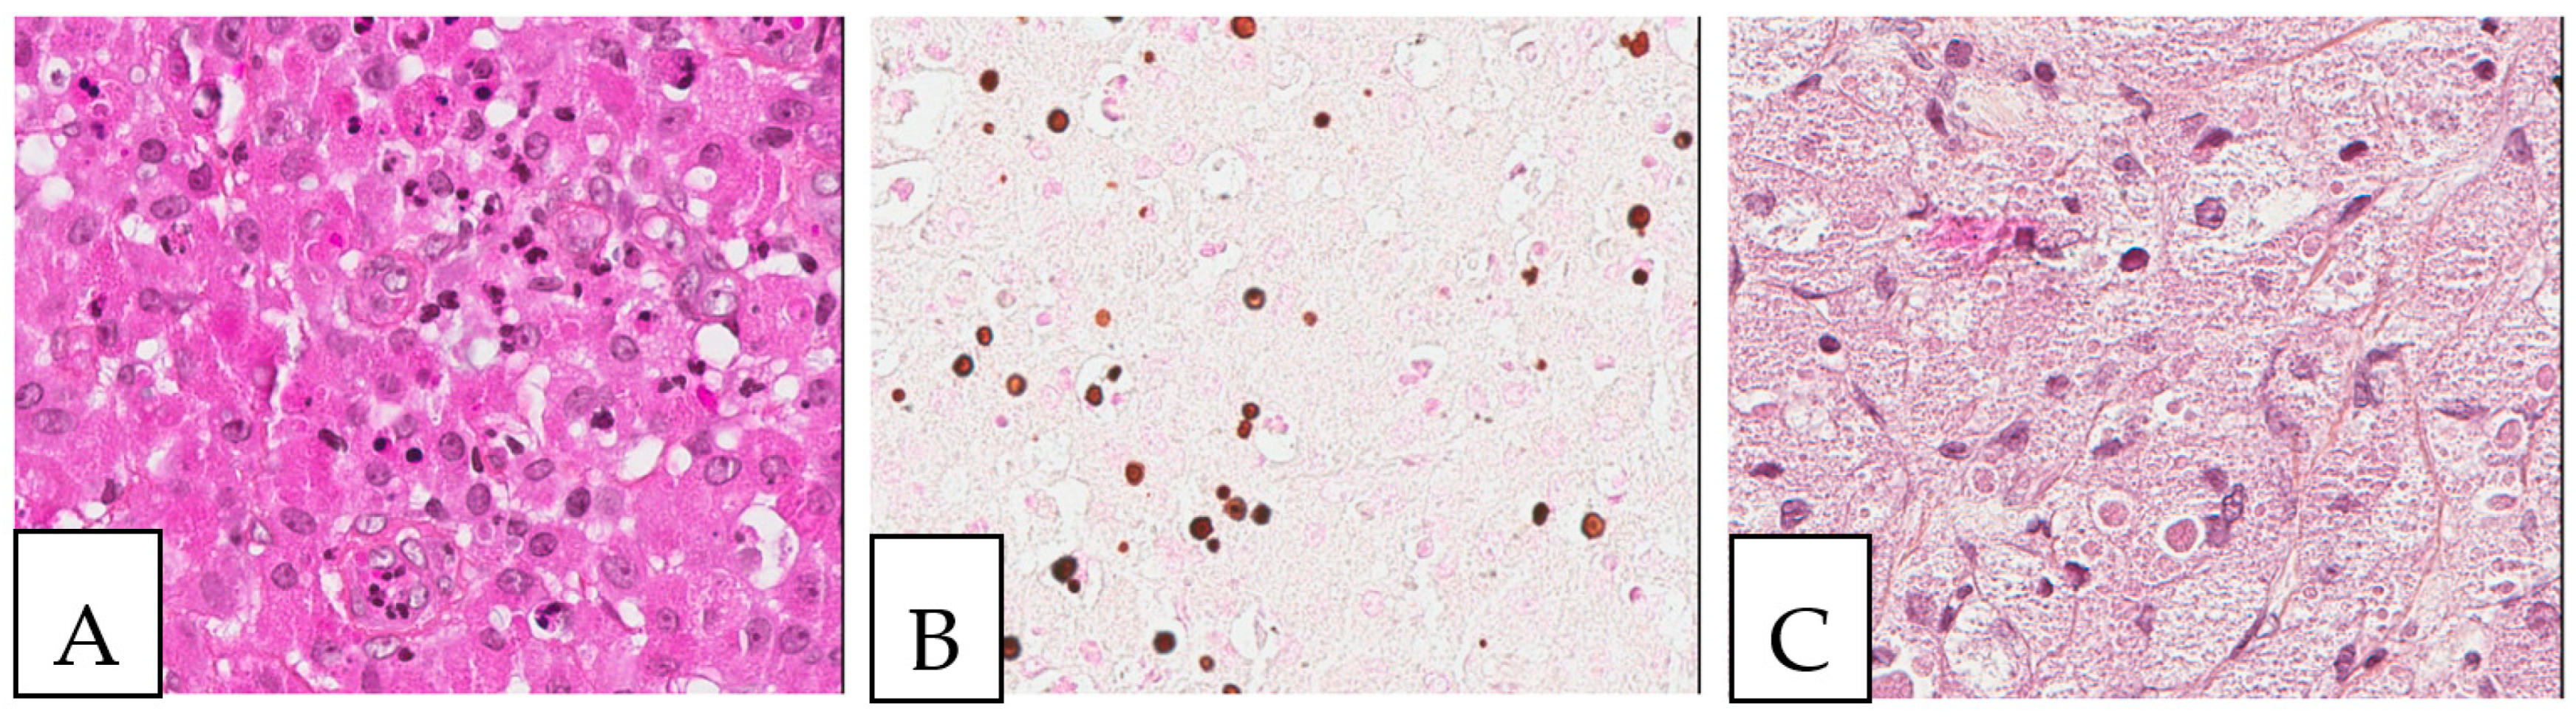

5. Pathologic Features